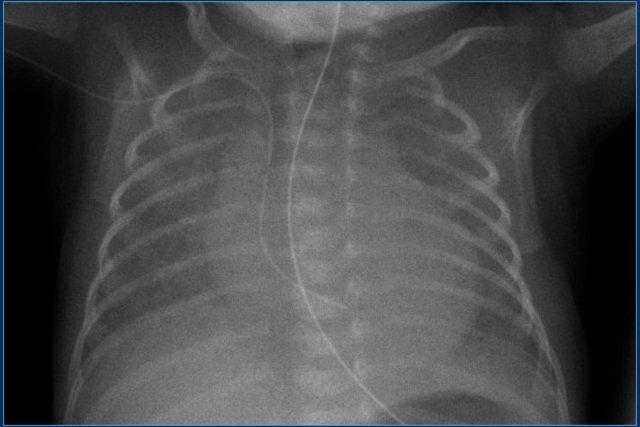

Các phát hiện bao gồm:

- PICC line đặt lạc chỗ trong nhĩ phải.

- PICC line đặt lạc chỗ.

Có thể nằm trong xoang vành hoặc trong nhĩ trái sau khi đi qua lỗ bầu dục còn thông.